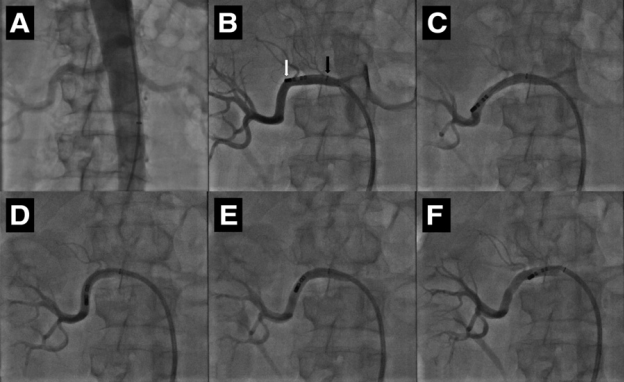

Hình 8: Kỹ thuật sử dụng ống thông đốt rối loạn nhịp thường quy triệt đốt thần kinh giao cảm động mạch thận trong nghiên cứu của Humera và cộng sự

30 bệnh nhân tăng huyết áp kháng trị (với số thuốc hạ áp trung bình đang sử dụng là 6) đã được chọn vào nghiên cứu. Trước thủ thuật, các bệnh nhân được đánh giá lâm sàng toàn diện và đo huyết áp liên tục trong 24 giờ cũng như các xét nghiệm về chức năng thận. Các bệnh nhân được chụp động mạch thận kiểm tra, những trường hợp có hẹp động mạch thận > 50% sẽ không tiếp tục tiến hành thủ thuật và loại ra khỏi nghiên cứu. Ống thông đốt được đưa vào động mạch thận qua đường động mạch đùi phải, triệt đốt được thực hiện lần lượt từ bên, mỗi động mạch thận sẽ được triệt đốt 6-8 điểm dọc theo chiều dài, thời gian đốt mỗi điểm là 60 giây, cường độ năng lượng sử dụng bắt đầu rất thấp và tăng dần lên tới 8-13 W, quá trình đốt được theo dõi chặt chẽ bằng các thông số nhiệt độ và trở kháng mô. Heparin TM được sử dụng nhằm duy trì ACT từ 250 đến 300 giây. Một số bệnh nhân xuất hiện cảm giác đau bụng khi đốt điện được sử dụng các thuốc giảm đau ngay trong thủ thuật. Sau khi các điểm triệt đốt đã hoàn tất, các tác giả tiến hành chụp kiểm tra lại động mạch thận 2 bên nhằm đánh giá các tổn thương mới xuất hiện.

Nghiên cứu thực hiện trên 10 bệnh nhân, tất cả được chụp động mạch thận kiểm tra và sau đó được triệt đốt thần kinh giao cảm động mạch thận 2 bên bằng ống thông điều trị RF có tưới lạnh. Hiệu quả hạ huyết áp được đánh giá bằng phương pháp đo huyết áp liên tục 24 giờ ở các thời điểm trước, sau 1 tháng, 3 và 6 tháng. Tất cả các bệnh nhân đều được chụp lại động mạch thận nhằm kiểm tra xem có tắc hẹp hay phình động mạch thận hay không. Các xét nghiệm thể dịch về chức năng thận cũng được đánh giá trước và sau thủ thuật.

Kết quả từ nghiên cứu này bước đầu cho thấy, về mặt nguyên tắc, có thể sử dụng các ống thông điều trị RF có tưới lạnh dùng để điều trị rối loạn nhịp triệt đốt an toàn và hiệu quả thần kinh giao cảm động mạch thận trong điều trị tăng huyết áp kháng trị.